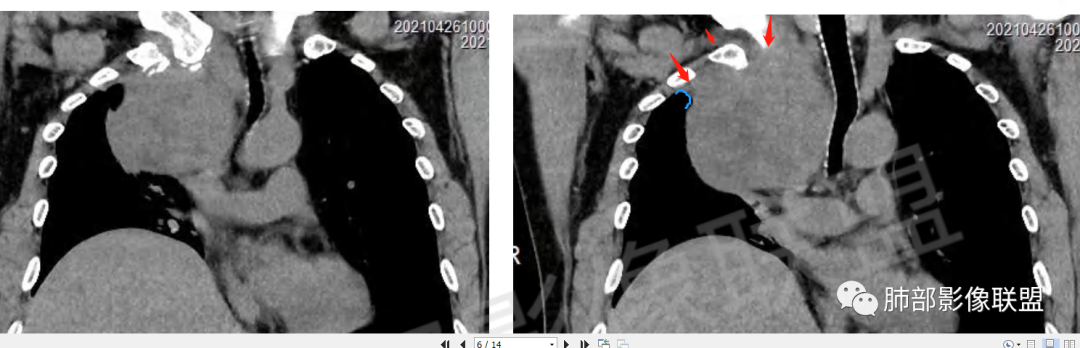

男,62,间断咳嗽4月。胸部CT:右侧胸腔大肿块,向内压气管,向前压上腔Ⅴ,向外挤压右上肺,右上肺体积缩小,瘤肺界面清楚,交界处可见压缩带,胸膜尾可见,平扫密度不均匀,增强可见大片低密度区,AB区?考虑肺外来源,N源性肿瘤(鞘瘤)?SFT?鉴别胸腺肿瘤,肺肉瘤等。

男,69岁,间断咳嗽4个月,右上肺体积缩小,可见巨大软组织占位,胸膜掀起,考虑来源于肺外,平扫密度不均匀,增强扫描明显不均匀强化,内部可见粗大血管及坏死区,周围组织受压移位。局部与食管分界不清,穿刺提示短梭形细胞,来源于间叶组织可能,综合考虑为神经鞘瘤>SFT

肿块把上腔静脉向前部推移,对肺内血管以及气管以推移为主,占位未见肺部血管供血,胸膜掀起处胸膜下脂肪间隙增宽,说明定位在肺外 SFT多为脏层胸膜起源,少部分壁层胸膜起源,壁层胸膜起源SFT不除外,但是胸膜掀起处胸膜下脂肪间隙增宽了,感觉SFT可能性比较小,这样囊变 AB区 纵膈神经起源的神经鞘瘤需要重点考虑,因为CT给的层不够,看不到肿瘤与椎间孔的关系,不敢确定,曾经病理提示高度考虑叶间起源肿瘤,肿瘤细胞呈短梭形细胞构成 不知道和神经鞘瘤是否符合!我重点考虑神经鞘瘤

边界清楚、光滑,D字征,与肺血管、支气管关系不密切,胸膜被掀起都提示肺外来源

上腔静脉受压前移

提示病灶来源于后方或纵隔外后方,

胸膜来源:孤立,大的边界清,首选SFT

纵隔:上腔静脉后方主要是膈神经,神经源性可以;后方局部与食道关系密切,食道来源肿瘤也可能,一般食道来源向前推移,这里推移方向不支持;气管受压,壁完整,软骨连续,气管单纯受压没有破坏,后方向内推移,不支持气管来源

粗大强化血管,主要看他起源,如果是来源肺动脉,肺内血管供血一是肺内二是脏层胸膜,肺内排除,只剩脏层胸膜SFT;如果这个是纵隔供血,那它可能是神经源性或者壁层胸膜,也可以是SFT比较少

从影像分析:SFT、神经鞘瘤鉴别可能大